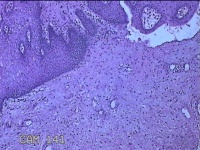

宫颈组织

性别

女

年龄

54岁

临床诊断

宫颈上皮内瘤变Ⅰ级

一般病史

反复阴道脱出肿物3年余。

标本名称

大体所见

灰白暗红色组织4.8x1.5x0.3cm一块,肥大,糜烂,切面灰白粉红色,质软